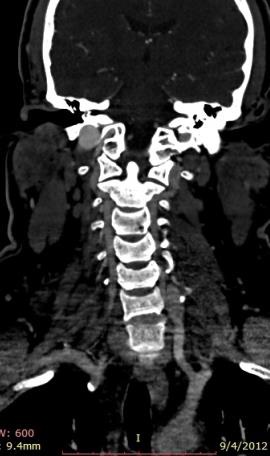

男40,近期颈部锐器伤后,2周来左侧颈部进行性肿胀。

冠状位增强,2D和3D,显示左椎动脉形成,可区别为什么不是颈内动脉与颈内静脉的动静脉瘘